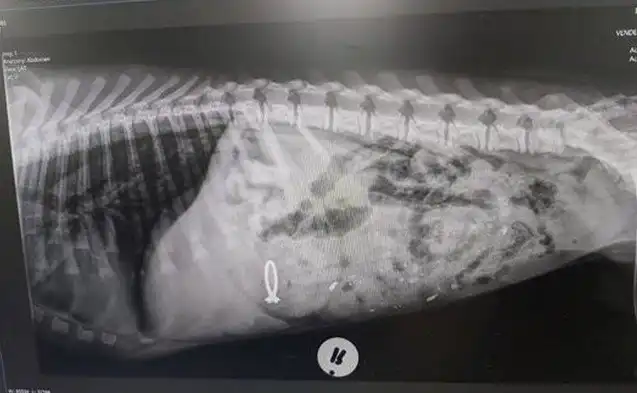

Ветеринарная клиника в южноафриканской Претории рассказала о необычном пациенте, который пришел с интересной проблемой – собака проглотила обручальное кольцо хозяйки. Его пришлось извлекать из животного проверенным способом.

«Меня зовут Пеппер. Я выгляжу так, будто мне плохо? Это потому, что ветеринар только что дал мне рвотное! Не потому, что ветеринар — злодей, а потому, что я съела обручальное кольцо моей мамы! — подписали снимок в клинике. — Не спрашивайте! Сперва это казалось хорошей идеей!».

Лекарство подействовало и уже через полчаса кольцо лежало перед собакой.